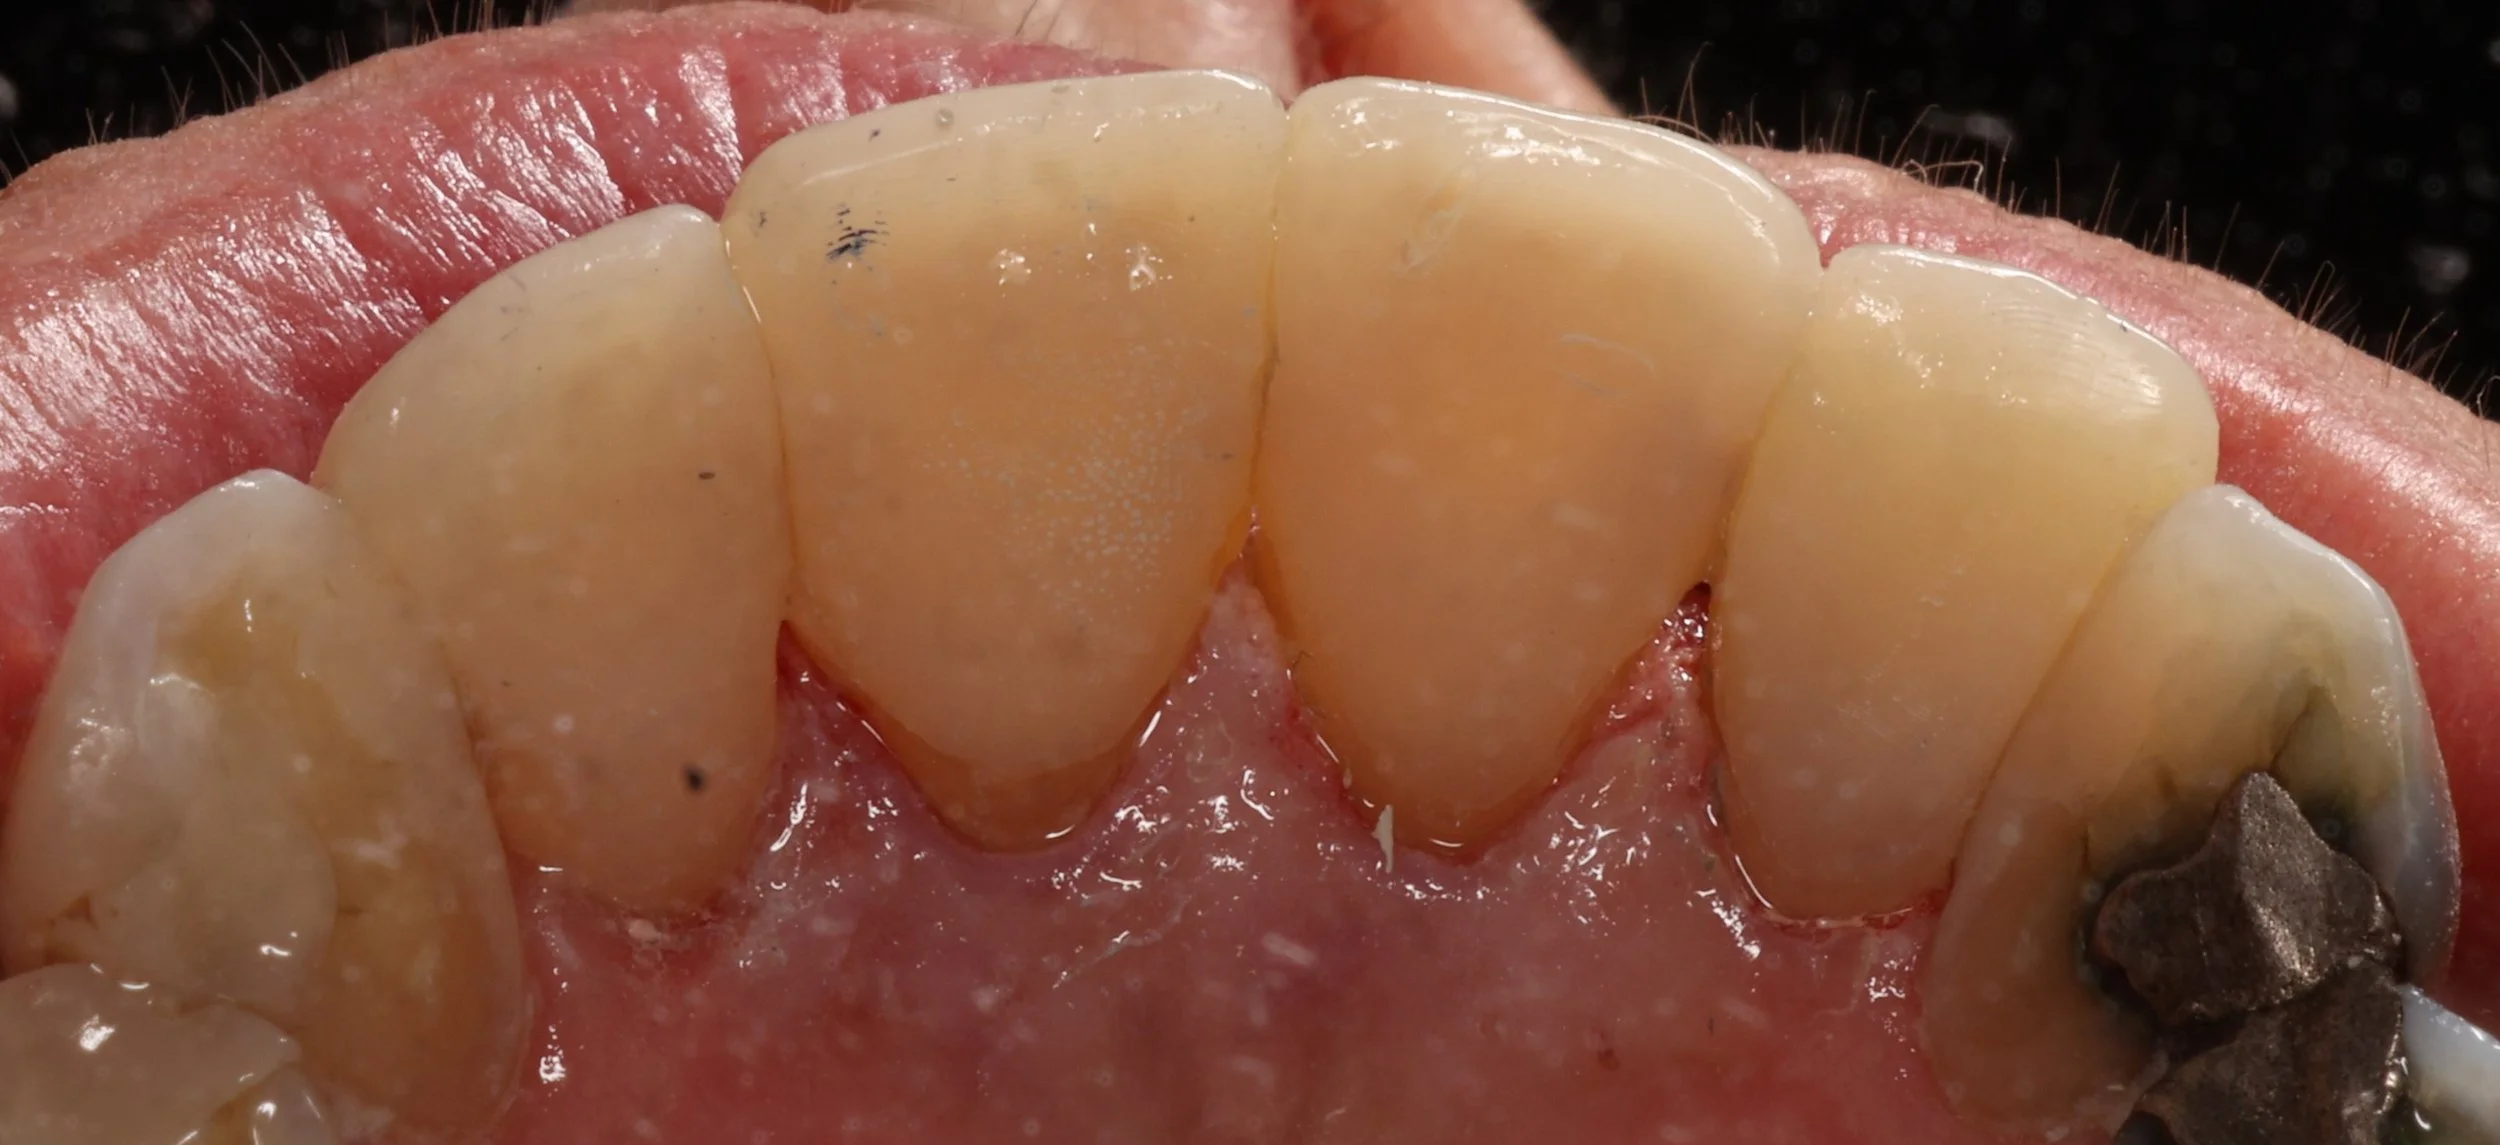

Injection moulding — guided by digitally planned smile design to achieve precise, natural, and minimally invasive results.

Injection moulding — combining digital smile design and biomimetic precision to recreate nature’s beauty with minimal intervention.